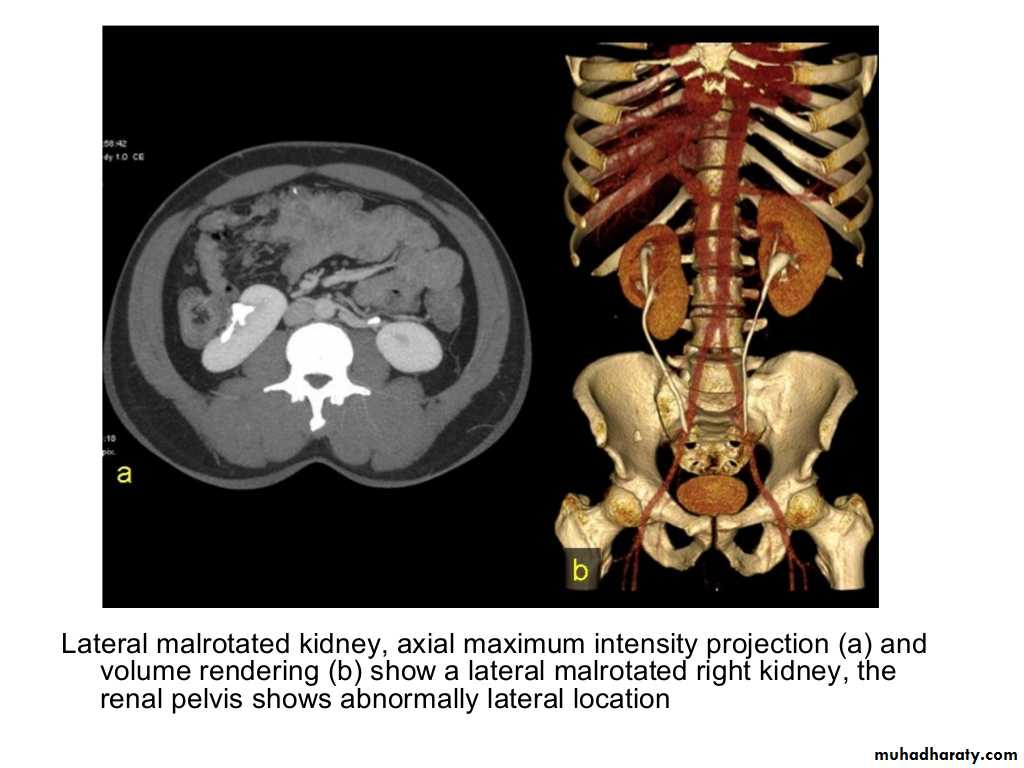

IVU shows

1. The kidneys at low position .2.Close to the spine with long axis parallel to the spine

3. Malrotation manifested by medially directed calyces.

4- The renal pelvis and ureters are anterior and lateral in position.

5- Hydronephrosis and calculi highly associated.